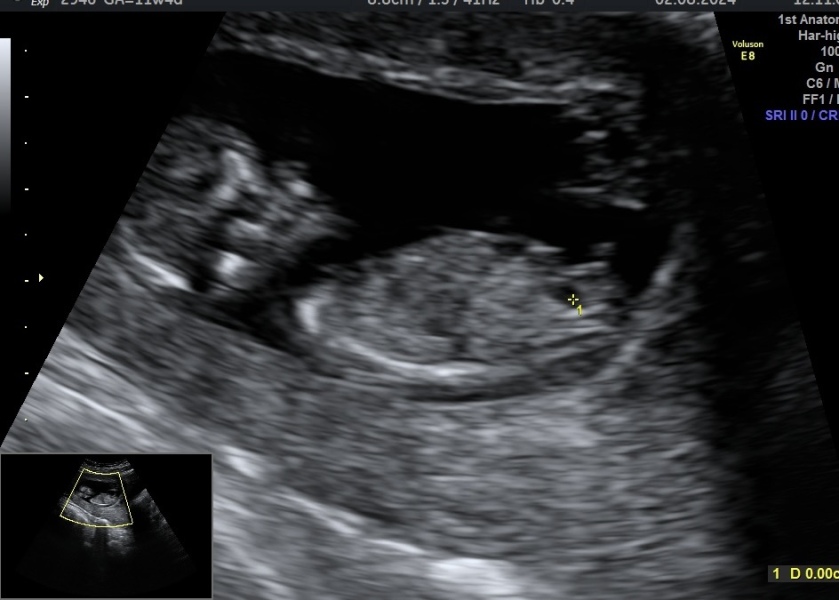

yesterday I had an ultrasound at 11 weeks and 4 days . I think the image is clear ! I would like to ask you your prediction about the gender !! Thank you in advance🙏🙏🙏